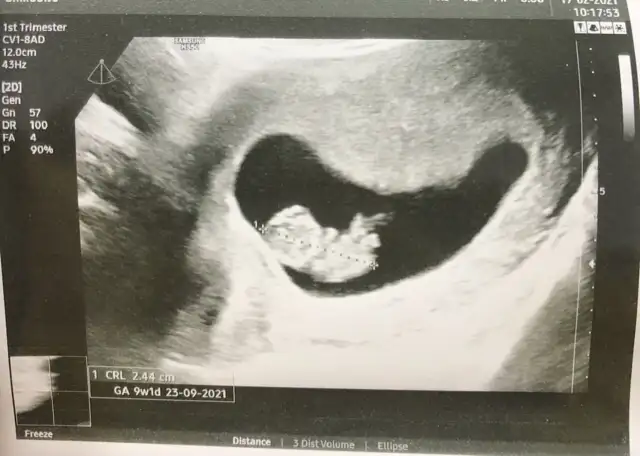

9+3 vajinal, ilk defa bebeğe benzettim koca kafasiyla 😅 yorumlamak isteyen 🤗

mde